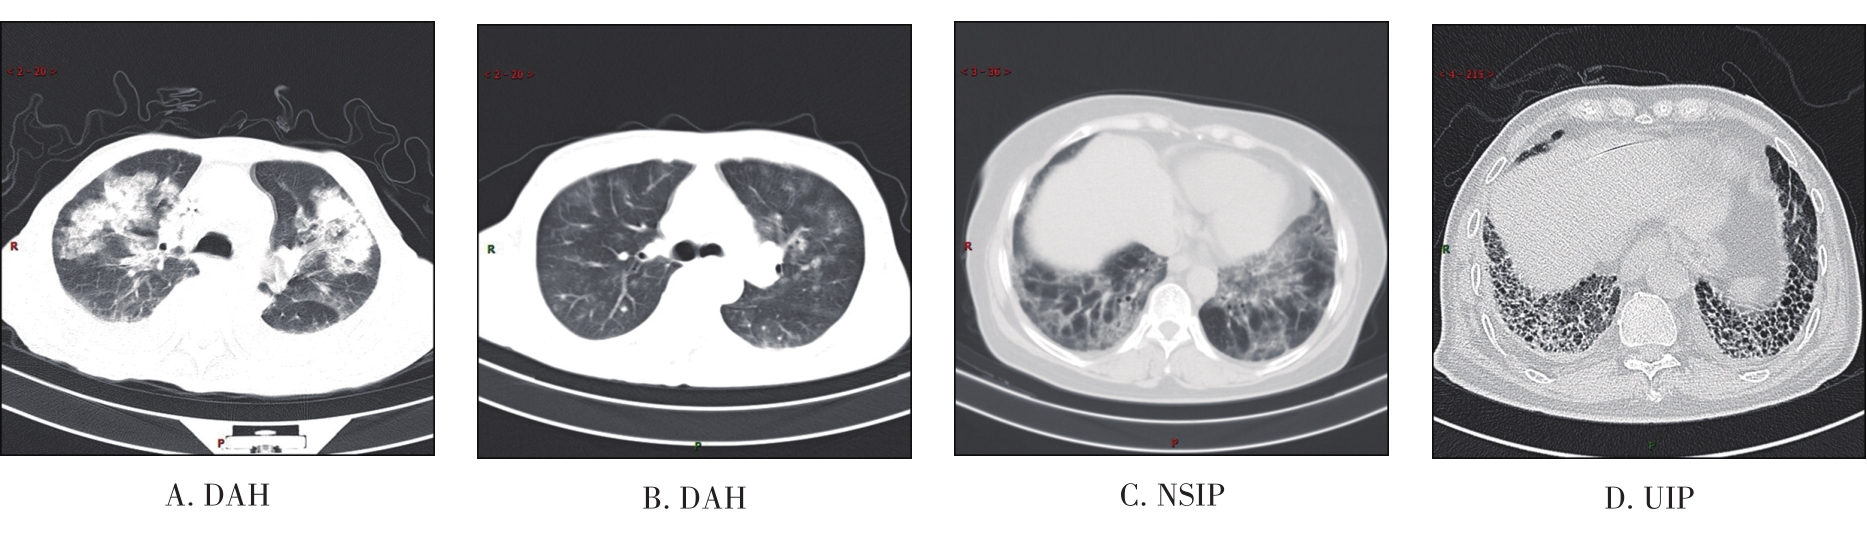

摘要:目的 探究显微镜下多血管炎(microscopic polyangiitis,MPA)肺受累的临床特征与预后因素分析。方法 回顾性分析2014年1月1日至2021年3月1日于重庆医科大学附属第一医院确诊及随访至2022年3月1日的237例MPA肺受累患者临床资料。采用Kaplan-Meier方法和Cox比例风险回归模型分析生存数据,得出累积生存率及预后因素。结果 MPA肺受累患者的平均年龄是65.18岁,中位随访时间为26.13个月。在纳入研究的237例患者中,MPA伴弥漫性肺泡出血(diffuse alveolar haemorrhage,DAH)患者98例(41.35%)。MPA肺受累患者1年、3年、5年累积生存率分别为67.50%、54.10%、43.00%。中位生存时间为45.03(0.10,97.73)个月。MPA伴DAH患者1年、3年、5年累积生存率分别为63.30%、49.40%、40.20%。Cox多因素回归分析显示年龄>65岁(HR=1.981,95%CI=1.244~3.154,P=0.004)、白细胞总数(white blood cell,WBC)>10×109个/L(HR=1.860,95%CI=1.170~2.956,P=0.009)、血清肌酐(serum creatinine,sCr)>250 μmol/L(HR=1.987,95%CI=1.217~3.243,P=0.006)、氧合指数<300 mmHg(HR=2.780,95%CI=1.696~4.557,P<0.001)、诊断时第三版伯明翰血管炎活动性评分(Birmingham vasculitis activity score version 3,BVASv.3)(HR=1.040,95%CI=1.006~1.075,P=0.020)是影响患者生存时间的独立预测因素(P<0.05)。结论 MPA肺受累患者生存率低下,年龄>65岁、WBC>10×109个/L、sCr>250 μmol/L、氧合指数<300 mmHg、诊断时BVASv.3是MPA肺受累预后不良的独立危险因素。